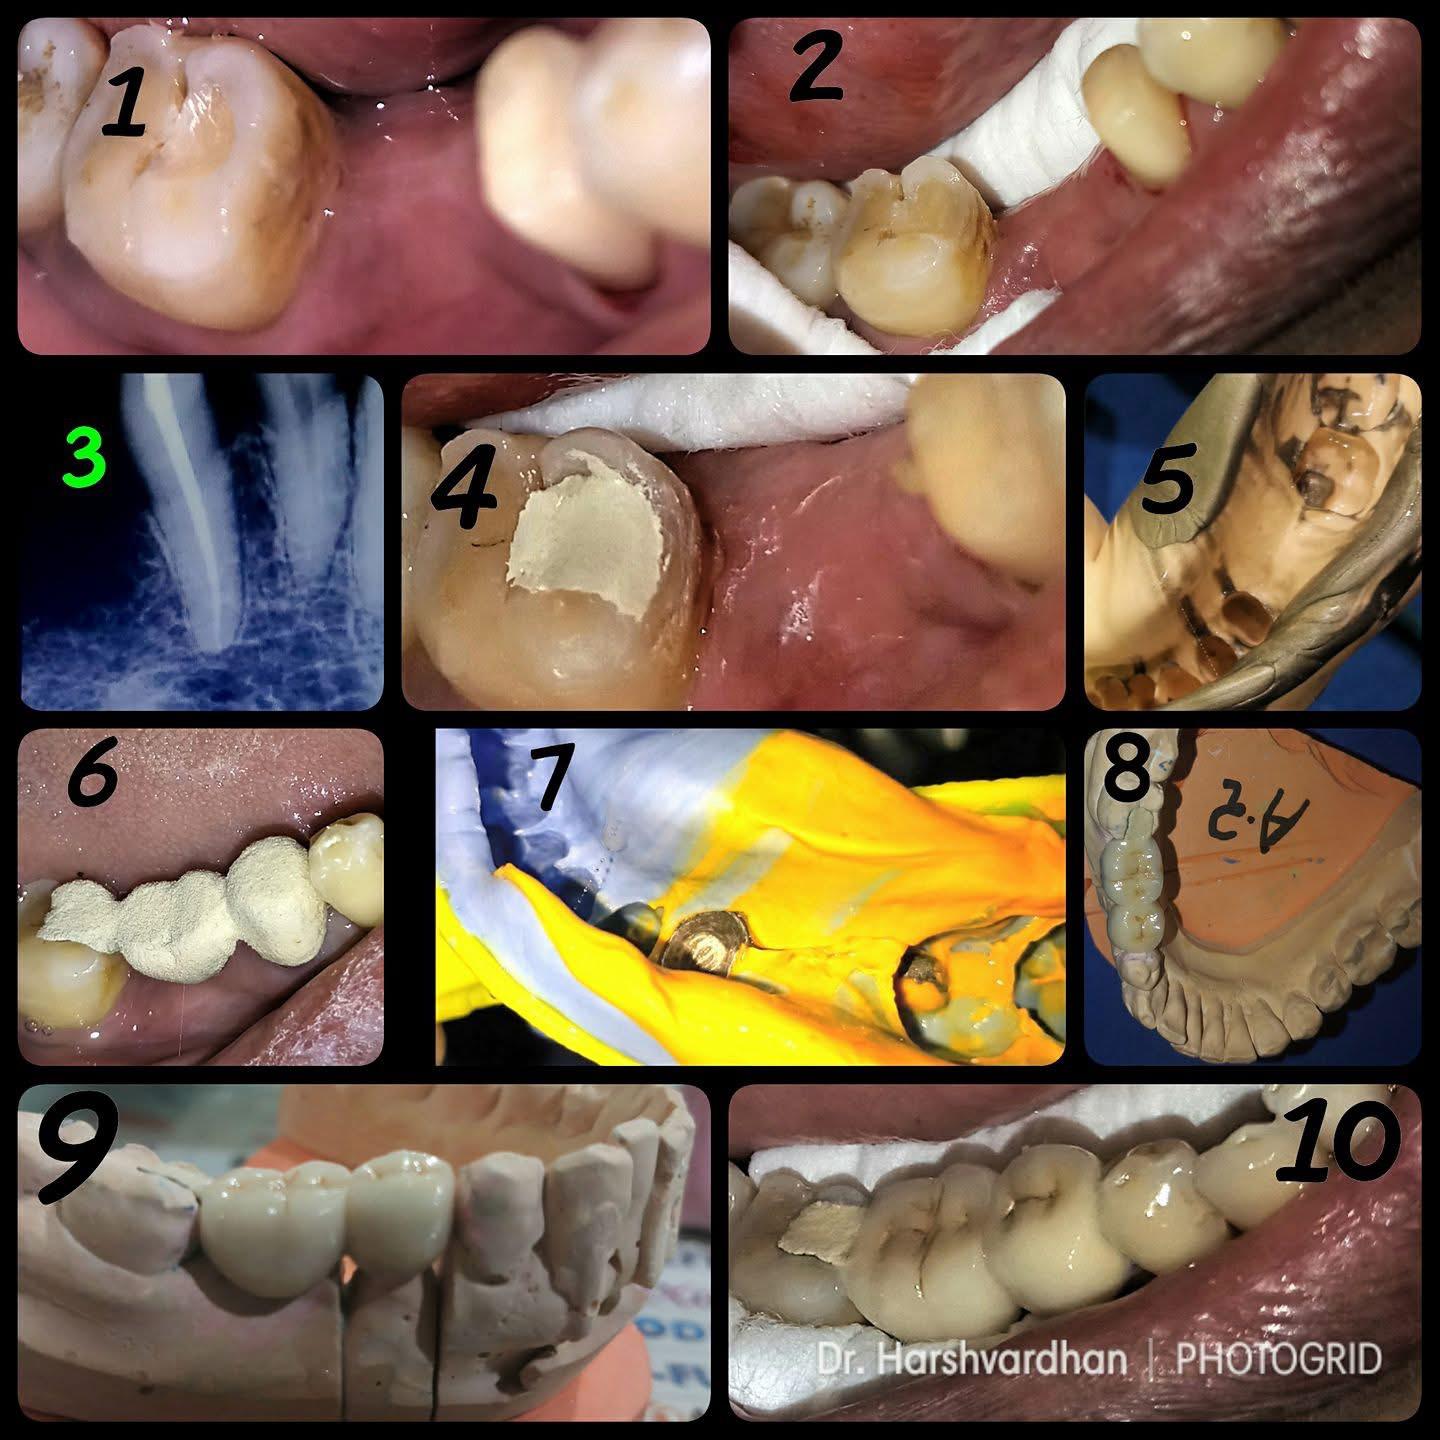

Clinical Cases